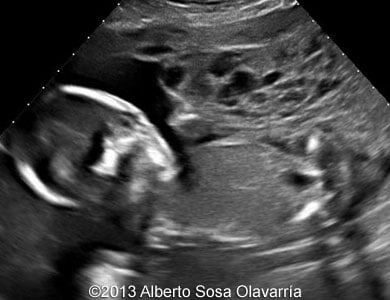

Case Presentation: Partial Molar Pregnancy

Case Presentation: Partial molar Pregnancy www.contemporaryobgyn.net

📃 Partial Molar Pregnancy

📃 Partial molar pregnancy thefetus.net